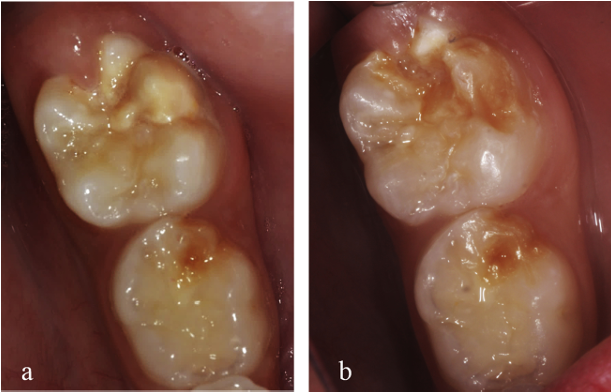

Participants returned at 1, 3, 6, 12, and 18 months after interventions. At these periods, VPI and DMFT were reassessed by the researcher (A), who was fully blinded regarding the assigned interventions. The teeth were photographed to compare enamel structural integrity throughout the subsequent evaluations (Fig. 2). The cut-off for the presence of carious lesions (CL) was determined using an ICDAS score ≥3, due to the difficulty of differentiating white spots lesions masked by MIH lesions. The same oral hygiene instructions given on the day of treatment were reinforced at all reassessments.

Fig. 2. Clinical aspect of a MIH-affected tooth (yellow opacity) treated with fluoride varnish therapy (FV) at a) baseline and b) after an 18-month follow-up period (For interpretation of the references to colour in this figure legend, the reader is referred to the web version of this article).